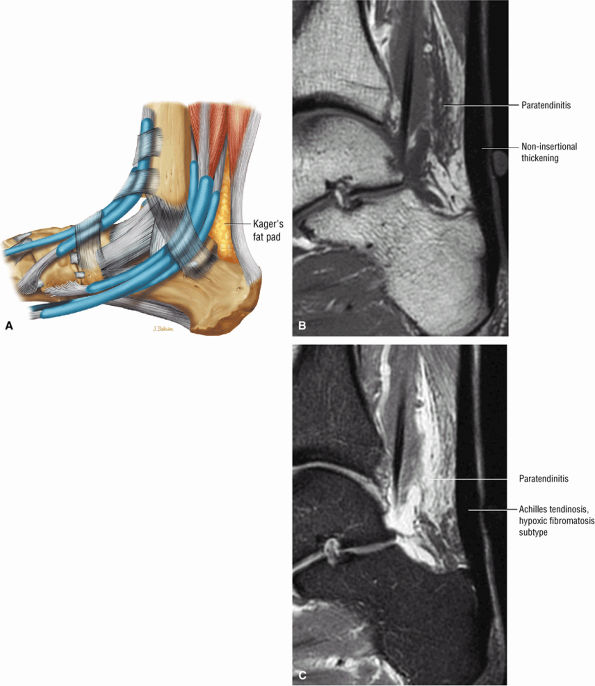

-

Achilles tendinitis is subdivided into non-insertional tendinosis and insertional tendinitis.

The Achilles tendon has no synovial sheath but is associated with a paratenon or connective tissue envelope.

MR identifies nodular or convex tendon thickening and intratendinous mucoid degeneration.

Haglund's deformity represents insertional tendinitis with a posterosuperior calcaneal bony prominence and retrocalcaneal tendo Achilles bursitis.

In tendinosis or tendinopathy, there is intrinsic or intrasubstance degeneration of the Achilles tendon.

Tendinitis represents the clinical symptoms that develop in association with the degenerative process of tendinosis.

In paratendinitis (also known as peritendinitis, since it refers to the peritendinous tissues), there is generalized inflammation of the tissues surrounding the Achilles tendon (pre-Achilles fat).32

In paratendinitis (peritendinitis) (Fig. 5.106) with tendinosis, there is inflammation of the surrounding tissues with associated tendon degeneration.

The paratenon (also referred to as the peritenon) represents the connective tissue envelope surrounding the Achilles tendon.

Paratenonitis is an inflammation of the Achilles tendon connective tissue envelope (usually limited to the posterior paratenon on MR images).

An irregular pre-Achilles fat pad may be seen with paratendinitis (peritendinitis) with or without abnormal Achilles tendon morphology.

Prominent anterior convexity with focal or diffuse thickening in the sagittal plane

Thickening and intermediate signal of peritendinous tissue dorsal, medial, and lateral to the Achilles tendon on T1- or PD-weighted images

Intermediate-signal-intensity effacement of peritendinous tissue anterior to the Achilles tendon on T1- or PD-weighted images

Hypointense to intermediate signal within an enlarged tendon in hypoxic fibromatosis (Fig. 5.111) on FS PD FSE images

Myxoid degeneration (Fig. 5.112) with increased signal on FS PD FSE or STIR images

Calcific (Fig. 5.113) or ossific degeneration with tendon thickening

Associated partial tears

Enthesopathic insertional tendinitis (Fig. 5.114)

Haglund's deformity (Figs. 5.115, 5.116, and 5.117) (insertional tendinitis with reactive calcaneal marrow edema [see Fig. 5.116], and the constellation of thickened tendon, retrocalcaneal/tendo Achilles bursitis, and a calcaneal bony prominence)

Effacement and edema of the pre-Achilles fat body with normal tendon morphology and/or signal

FIGURE 5.106 ● (A) Lateral color graphic of the normal anatomy of Kager's fat pad. Fat deposition deep to the Achilles tendon separates it from the deep compartment of the leg. Paratendinitis (also referred to as peritendinitis) demonstrates hypointensity and effacement of pre-Achilles fat on a sagittal T1-weighted image (B) and hyperintensity of the anterior soft tissue on a sagittal FS PD FSE image (C).

FIGURE 5.107 ● Non-insertional chronic Achilles tendinosis on sagittal T1-weighted (A) and FS PD FSE (B) images. Chemical inflammation is not involved in chronic Achilles tendinosis. Increased levels of the excitatory neurotransmitter glutamate and lactate, however, have been demonstrated in painful midportion tendinosis.

FIGURE 5.108 ● Insertional tendinitis with hyperintensity of the thickened distal Achilles tendon. Retrocalcaneal bursal inflammation and calcaneus marrow edema are shown. In contrast to non-insertional degenerative tendinosis, the process of insertional Achilles tendinitis demonstrates an inflammatory process histologically. Achilles enthesopathy is another term for insertional Achilles tendinitis. FS PD FSE (A) sagittal and (B) axial images.